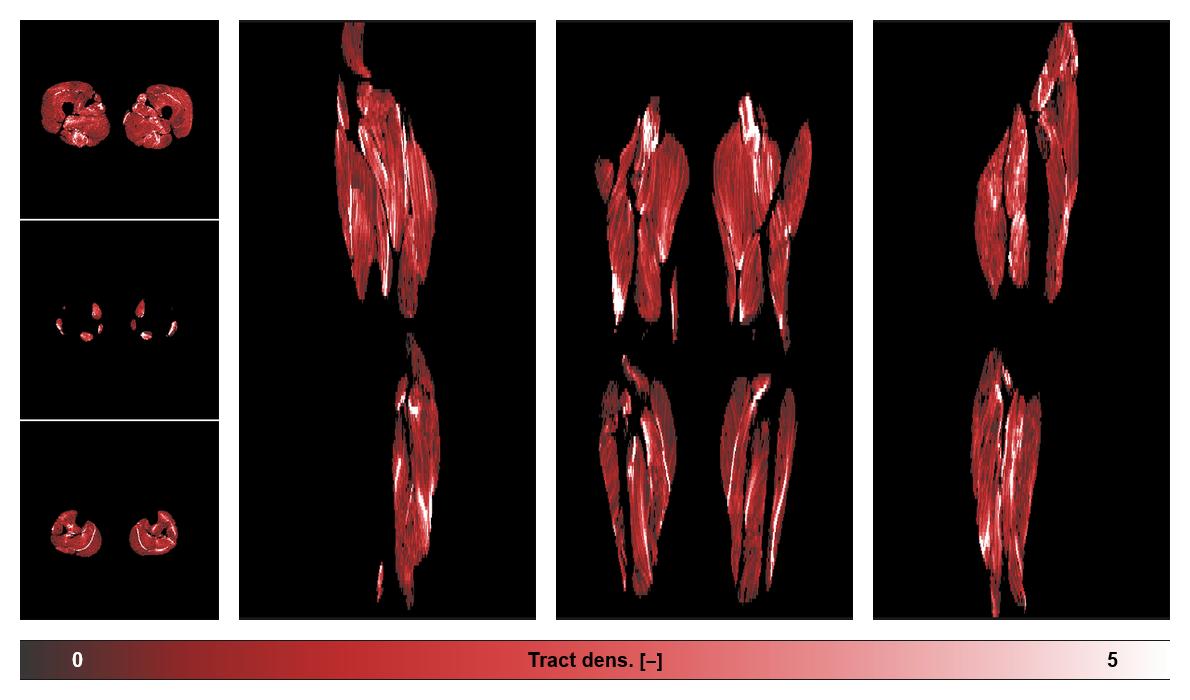

• Muscle fiber density map

Muscle fiber tract density map based on whole leg DTI based fiber tractography.